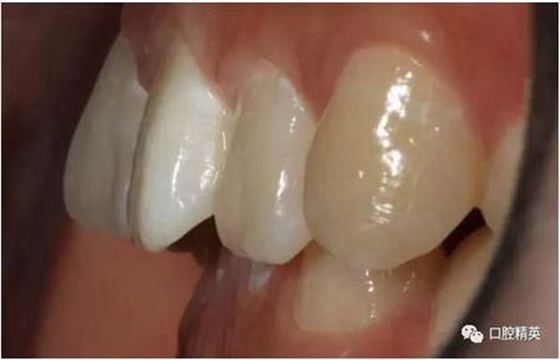

口內(nèi)正側(cè)位及切端特寫(xiě)

從側(cè)位照可看出遠(yuǎn)中切角略有回收

術(shù)前,術(shù)中,術(shù)后對(duì)比

對(duì)比來(lái)看基本達(dá)到患者預(yù)期